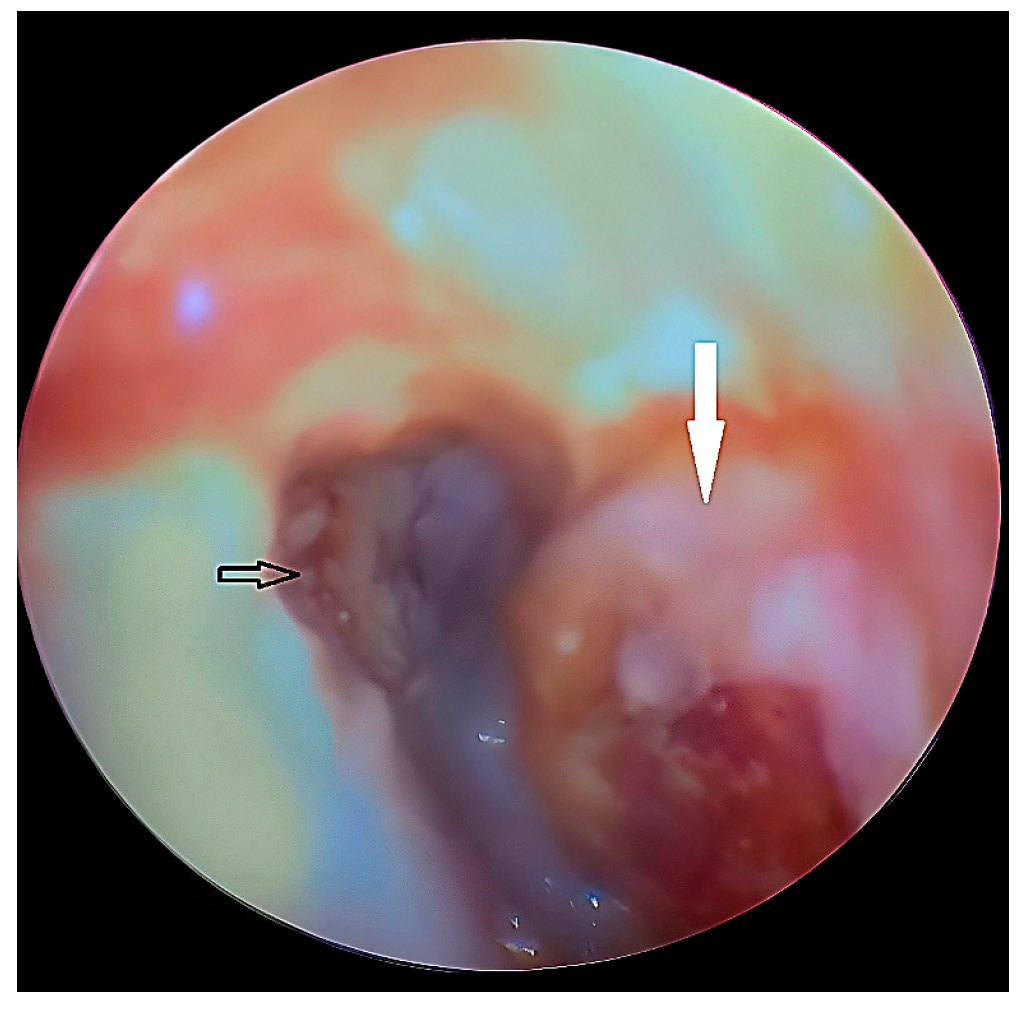

- Case 5

| 5 | Female | 45 | External auditory canal abscess |

OPG CT/MRI | 10 mm | Incision and drainage of the abscess | 51 mm |